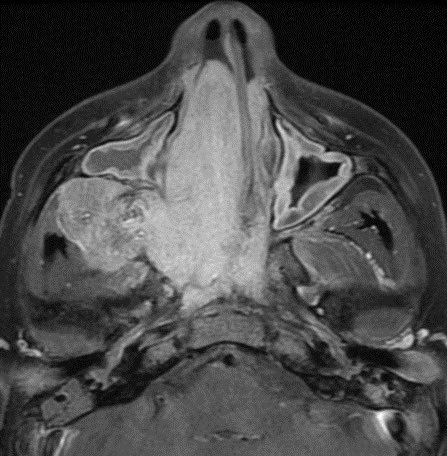

⭐️ Classic case: what’s the most likely diagnosis in this 12 y/o M presenting with stuffy nose and epistaxis? #ENT #Peds #medicine #radres #futureradres #Neurology #neurosurgery @ASHNRSociety @Radiopaedia

⭐️ Classic case: what’s the most likely diagnosis in this 12 y/o M presenting with stuffy nose and epistaxis? #ENT #Peds #medicine #radres #futureradres #Neurology #neurosurgery @ASHNRSociety @Radiopaedia